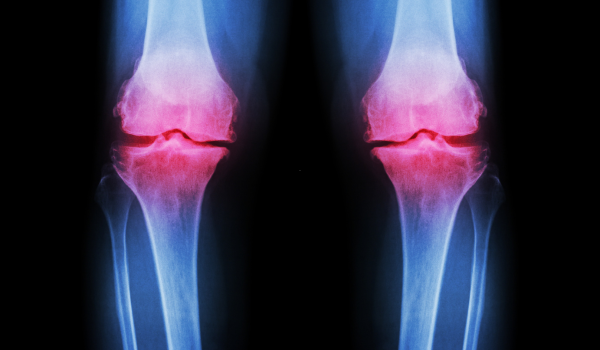

Osteoarthritis (OA) and rheumatoid arthritis (RA) are two of the most common types of arthritis — both cause joint pain and stiffness, but they develop for very different reasons.

Osteoarthritis occurs when the protective cartilage that cushions your joints wears down over time. This type of arthritis is degenerative, meaning it results from gradual wear and tear.

Rheumatoid arthritis, on the other hand, is an autoimmune disease — your body’s immune system mistakenly attacks the lining of your joints, leading to inflammation, swelling, and joint damage.

Osteoarthritis typically develops gradually and often affects one side of the body, while rheumatoid arthritis tends to appear symmetrically (on both sides) and may also cause fatigue or fever.